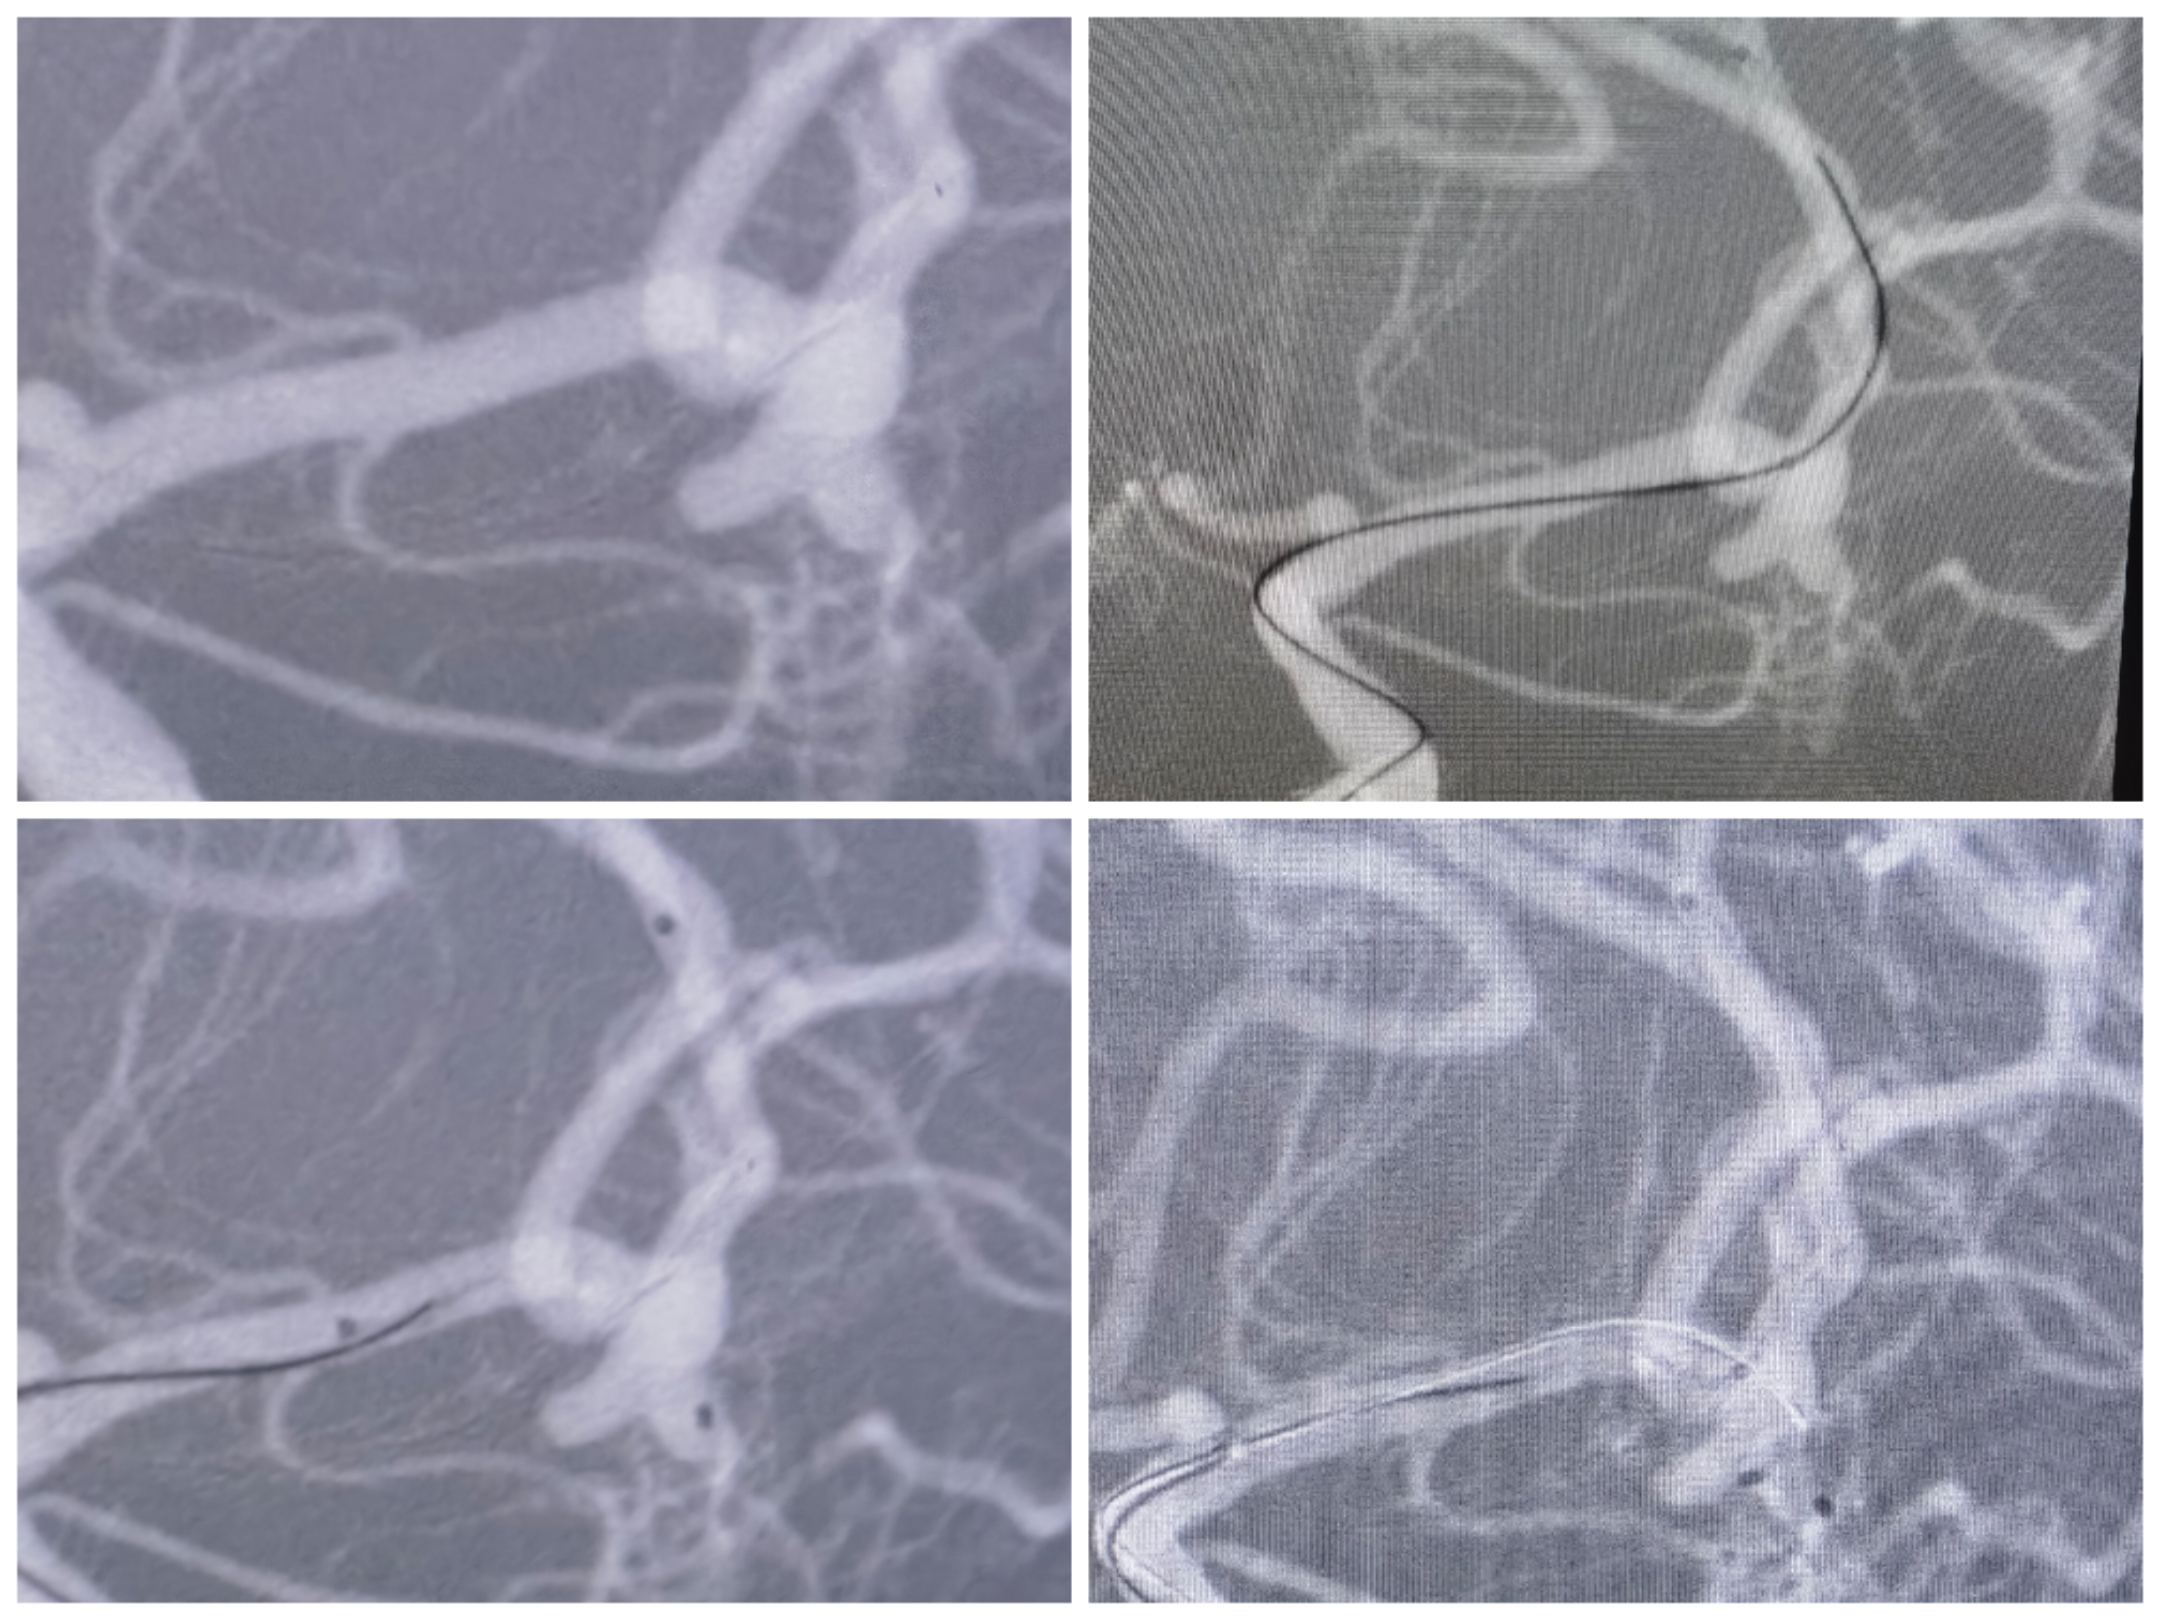

右侧颈内造影提示后交通不规则动脉瘤

椎动脉造影提示右侧P1良好,无需刻意保留后交通动脉

3D重建情况

拟支架辅助+双微管栓塞,微导管布局情况

先栓塞远端子囊+支架释放,双微管交替栓塞

栓塞术后情况